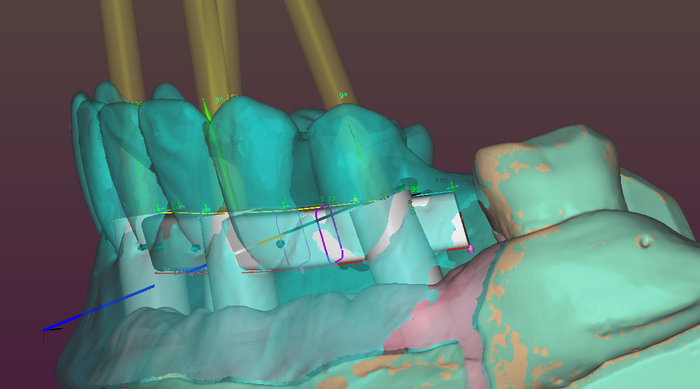

Балку получил из фрезерного центра, теперь надо её проверить на качество "посадки" на аналоги имплантов и в случае если будет баланс припассовать.

Титановый каркас "сидит" как надо не качается и не балансирует; не только на лабораторной модели, но и в полости рта — можно продолжать.